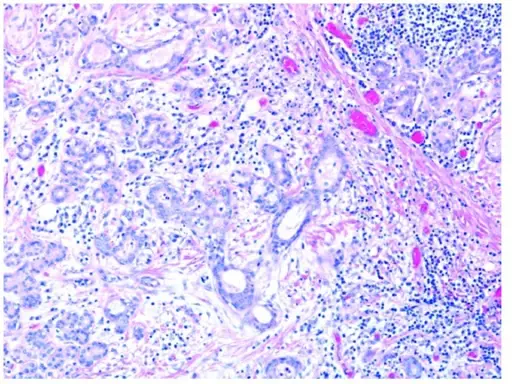

Pleomorphic Adenoma

Pleomorphic adenoma is a benign tumor made up of both epithelial and stromal tissue.

Pleomorphic adenoma is the most common salivary gland tumor.

Pleomorphic adenoma appears as a moving, painless mass that is constrained to the angle of the jaw.

Histologically pleomorphic adenomas have a myxoid component and a stromal component.

Pleomorphic adenoma is associated with the PLAG1 gene mutation.

Treatment of pleomorphic adenoma is surgical resection.

Small islands of tumor that extend through the tumor capsule frequently result in an incomplete resection.

There is a high recurrence rate for excised pleomorphic adenomas.

Rarely the benign pleomorphic adenomas may develop into their malignant counterparts carcinoma-ex pleomorphic.